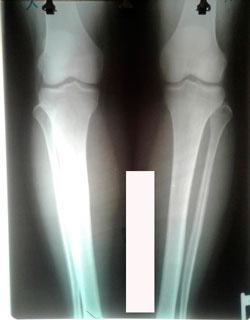

Исходник - 44 года.

Дата операции - 02.09.2020

image-03-09-20-11-09.jpg

image-01-09-20-02-12.jpg